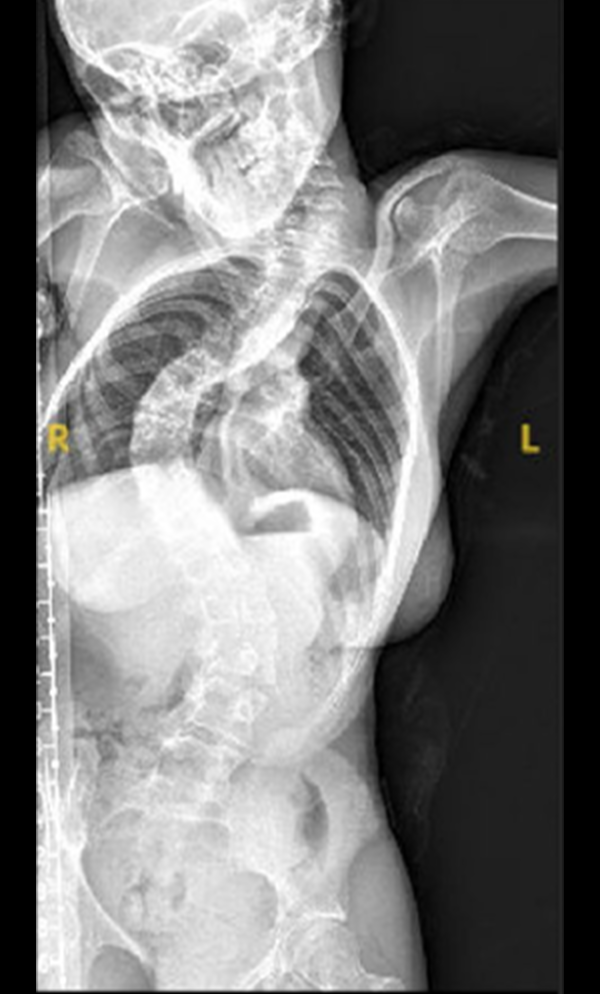

Gallery : Before - After